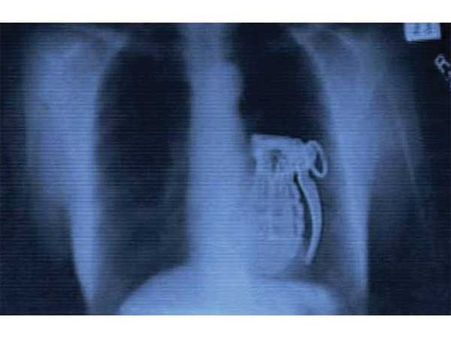

হাতবোমা

অনেক সময় চোরা চালানকারীরা পেটে জিনিসপত্র লুকিয়ে পাচার করে। কিন্তু এক জঙ্গি পেটে হাত বোমা দেখা গিয়েছিল।